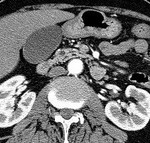

[画像診断]膵IPMN国際診療ガイドラインによる治療、経過観察指針について 2011-01-26